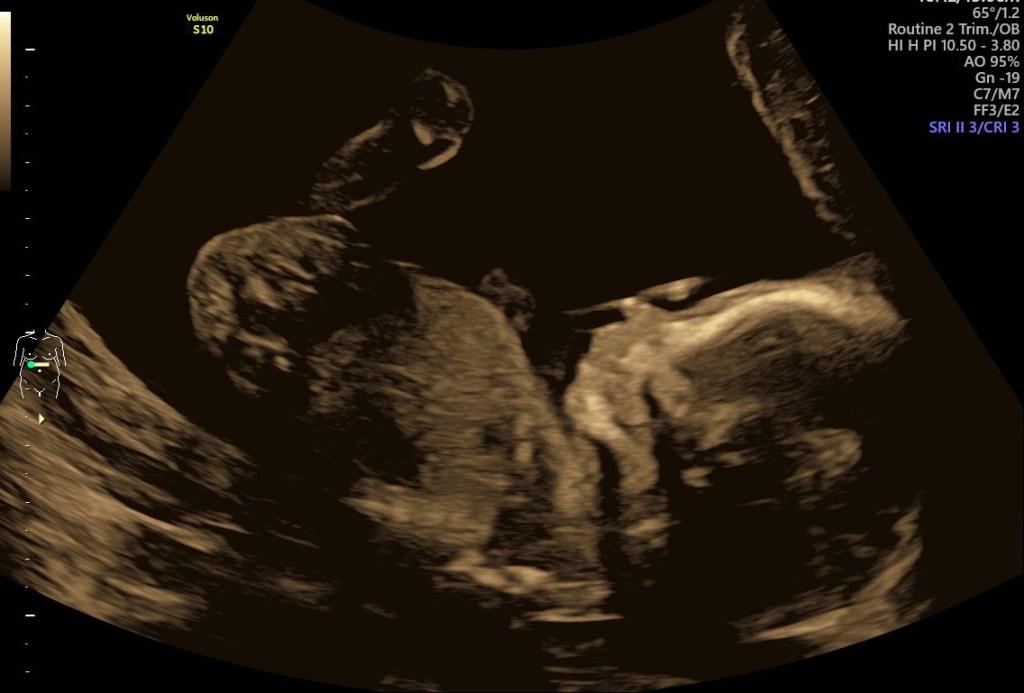

About 8 weeks later (at 20 weeks), he is 20-25 cm, 300 grams and the size of a pointed bell pepper: